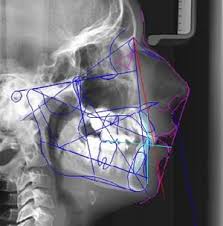

Prévention et interception des malocclusion

2 examensExamens disponibles

CC ODF

ODF qcm

Dysmorphoses et malocclusions

7 examensExamens disponibles

Dysmorphose et malocclusion #1

Dysmorphose et malocclusion #2

Dysmorphose et malocclusion #3

Dysmorphose et malocclusion #4

Dysmorphose et malocclusion #5

Dysmorphose et malocclusion #6

Dysmorphose et malocclusion #7